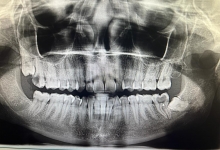

Clinica LUY ESTHETIC ART defineste parodontoza ca fiind rezultatul direct al placii dentare, care se depune pe suprafata dintilor, dar si in apropiere de marginea gingivala. Aceasta boala duce la pierderea dintilor, chiar daca ei sunt aparent sanatosi si nu prezinta carii. Edentatiile, afecteaza vorbirea, aspectul, dar si capacitatea de a mesteca.

Boala parodontala are un caracter progresiv. Pentru cazurile mai grave, recomandam tratamentul parodontal chirurgical rezectiv sau regenerativ.

Recomandam controale periodice (3-6 luni) pentru igienizari profesionale: detartraj, periaj dentar, air-flow etc. Aceste operatiuni asigura sanatatea gingiei, iar osul alveolar si ligamentele parodontale isi pastreaza integritatea.